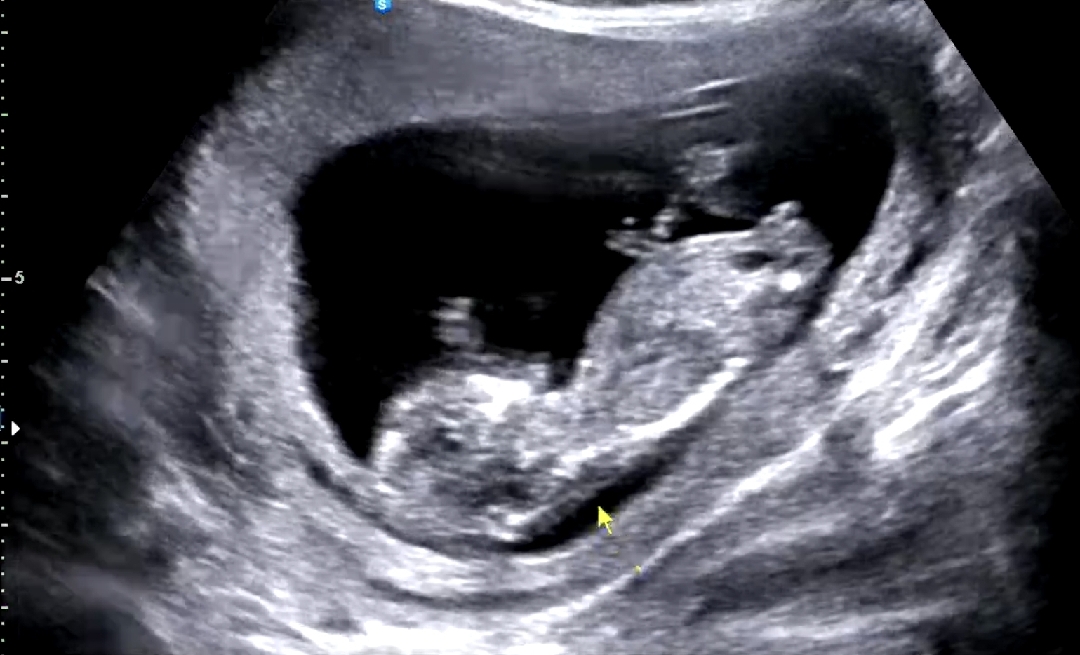

성별 알수있나요? 각도법?

매끈한게 딸같은데 어떤가요?ㅎㅎ

딸 축하드려요

딸이네요